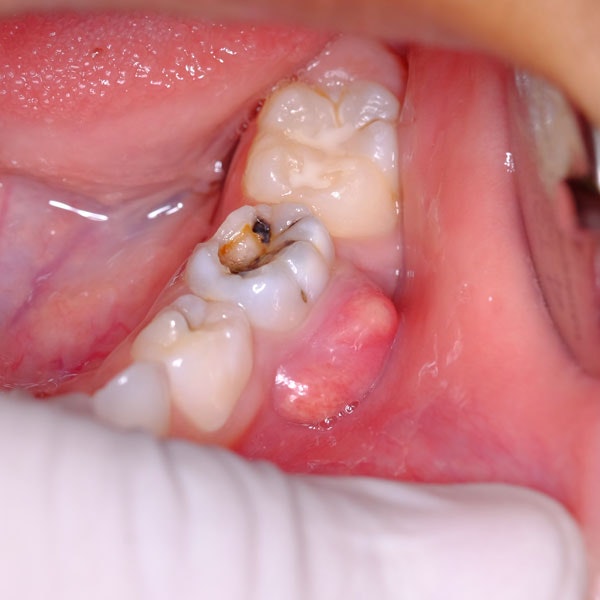

Receive a Simple Extraction

Non-impacted teeth are removed with a simple extraction that doesn't require an incision in the gums. After sedation and numbing, the dentist will gently rock the tooth back and forth out of the socket. Gauze is applied to help the blood clot and no stitches are required to stop the bleeding.

Receive a Surgical Extraction

The dentist may need to create an incision in the gums and remove bone tissue to access the impacted tooth for complex oral problems. In some cases, the tooth will need to be removed in pieces. Depending on the severity, you may need stitches. Again, gauze will be applied to help stop the bleeding.